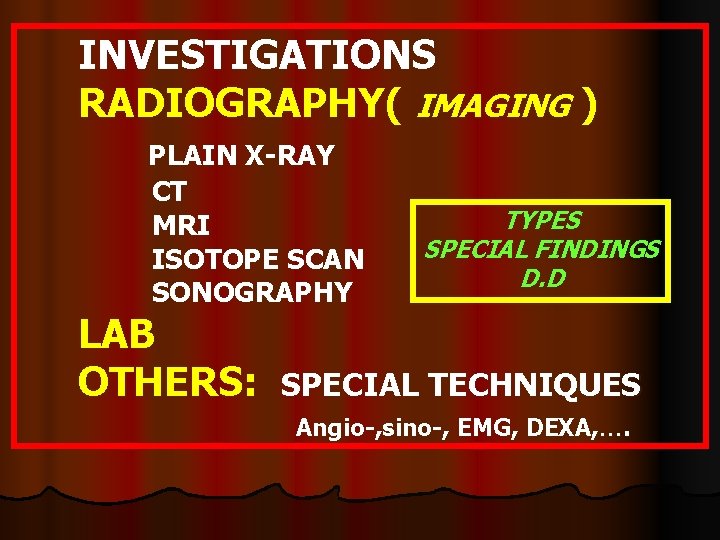

INVESTIGATIONS RADIOGRAPHY( IMAGING ) PLAIN X-RAY CT MRI ISOTOPE SCAN SONOGRAPHY LAB OTHERS: TYPES SPECIAL FINDINGS D. D SPECIAL TECHNIQUES Angio-, sino-, EMG, DEXA, ….